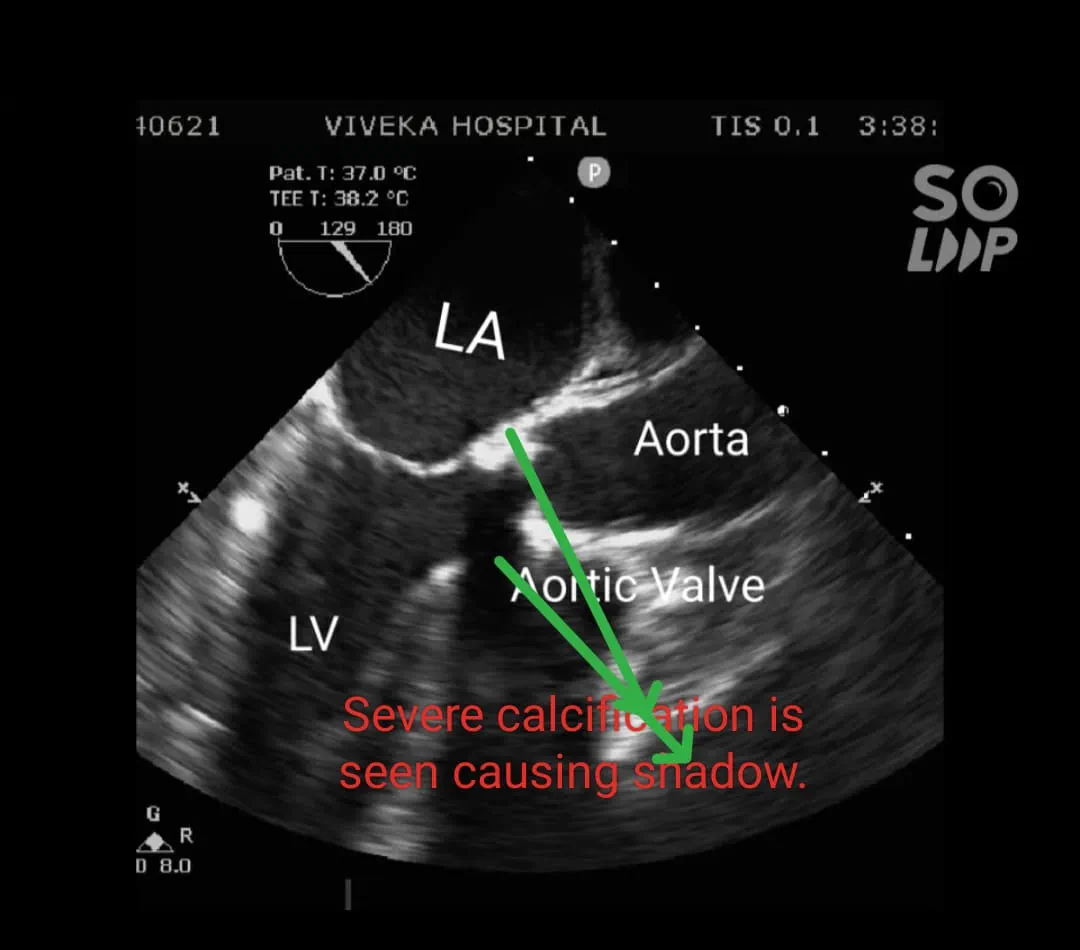

Transoesophageal echocardiography: Findings of Transthoracic ECHO confirmed. Aortic annulus : 20.1mm

Gradient : 128/50 mm of Hg. Mild Aortic regurgitation. Severe Concentric Left ventricular hypertrophy. Calcific Aortic Valve with area 0.349 cm2.

Findings after opening aorta: Aortic Valve was bicuspid and heavily calcified. Indigenous aortic valve excised and calcium debrided.